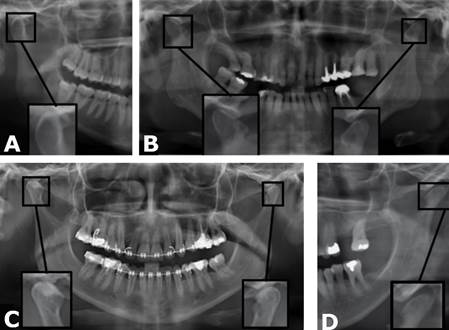

Se utilizan radiografías para visualizar la estructura ósea de la ATM, identificar problemas estructurales y evaluar la salud de la articulación.

Evaluación radiográfica de la articulación temporomandibular (ATM)